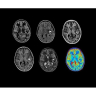

• NeuroWorks — универсальное решение для визуализации анатомии головного мозга, позвоночника, сосудов и периферических нервов с четкой дифференциацией тканей.

• ImageWorks — повысит производительность МРТ благодаря визуализации высокого качества с MAGIC, четкими результатами пост-процессинга с READYView.